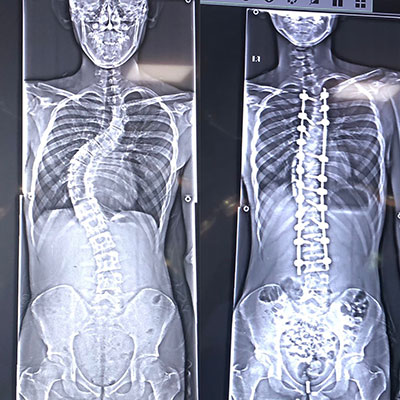

Skolyoz, omurganın yandan bakıldığında S veya C şeklinde eğrilik gösterdiği bir omurga hastalığıdır. Genellikle çocukluk ve ergenlik döneminde başlayan bu durum, omurganın düzgün hizalanmasını engeller. Skolyozun nedeni tam olarak bilinmese de, çevresel, genetik veya nöromüsküler faktörlerle ilişkili olabileceği düşünülmektedir. Hafif vakalardan ciddiye kadar değişen şiddette görülebilir ve bazı durumlarda belirti vermeden ilerleyebilir. Ancak ilerleyen vakalarda, omurga eğriliği ve eşlik eden postür bozukluğu nedeniyle fiziksel rahatsızlıklara, sırt ve bel ağrısına, solunum güçlüklerine ve organlara baskıya neden olabilir. Erken teşhis ve tedavi, skolyozun ilerlemesini engellemeye ve yaşam kalitesini artırmaya yardımcı olabilir.

Omurganın ön ve arkadan bakıldığında 8 - 10 derece üzerindeki sağ veya sol tarafa olan eğriliği ile buna eşlik eden, kendi ekseni etrafındaki dönme hareketinin (rotasyon ) oluşturduğu bir şekil bozukluğudur. Skolyoz omurga deformiteleri içerisinde en sık karşılaştığımız ve ilerleyen evrelerde ciddi duruş bozukluklarına neden olan üç boyutlu bir omurga deformitesidir.